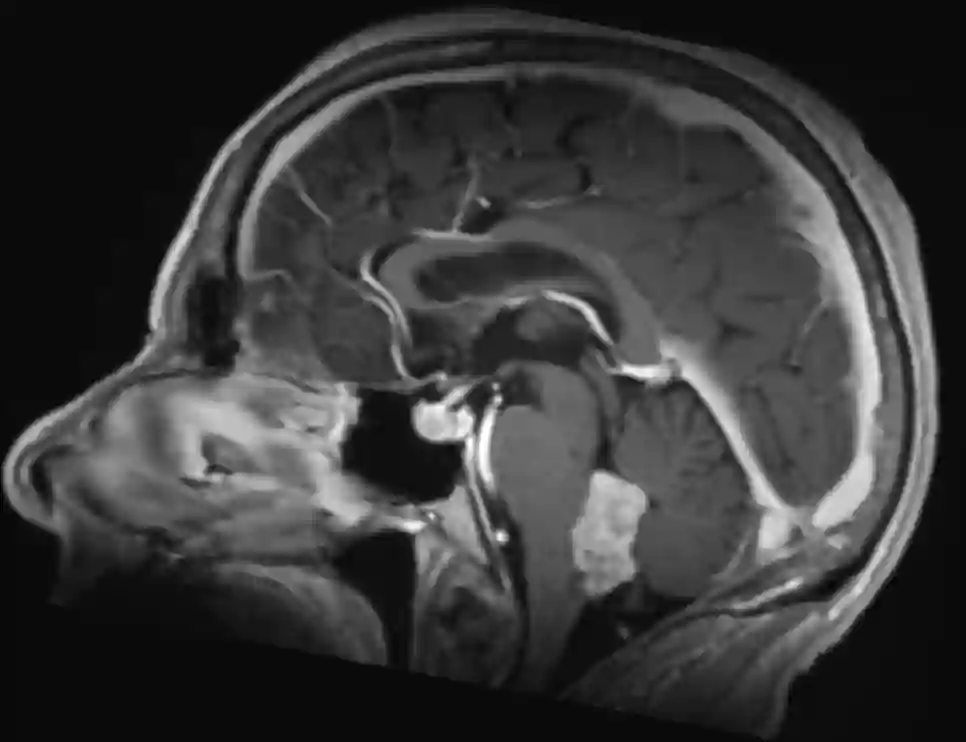

Zwei Drittel der Ependymome treten infratentoriell im 4. Ventrikel auf, das übrige Drittel liegt supratentoriell und zumeist in der periventrikulären weißen Substanz. Im Gegensatz zu einem Medulloblastom, welches häufig vom Dach des 4. Ventrikels ausgeht, breitet sich ein Ependymom oft vom Boden des 4. Ventrikels aus.

Bildgebend unterscheiden sich Ependymome von Medulloblastomen vor allem durch die häufige Kalzifikation, welche bei Medulloblastomen nur in weniger als 10 % der Fälle vorkommt[^2]. Ebenso zeigen sich Ependymome häufig inhomogen in der T1 Sequenz und die exophytische Komponente zeigen sich bei Ependymomen oft hyperintenser in der T2 Sequenz[^2]. Ependymome können in der MRT Bildgebung eine Diffusionsrestriktion aufweisen, was jedoch bei Ependymomen deutlich seltener als bei Medulloblastomen vorkommt[^4].